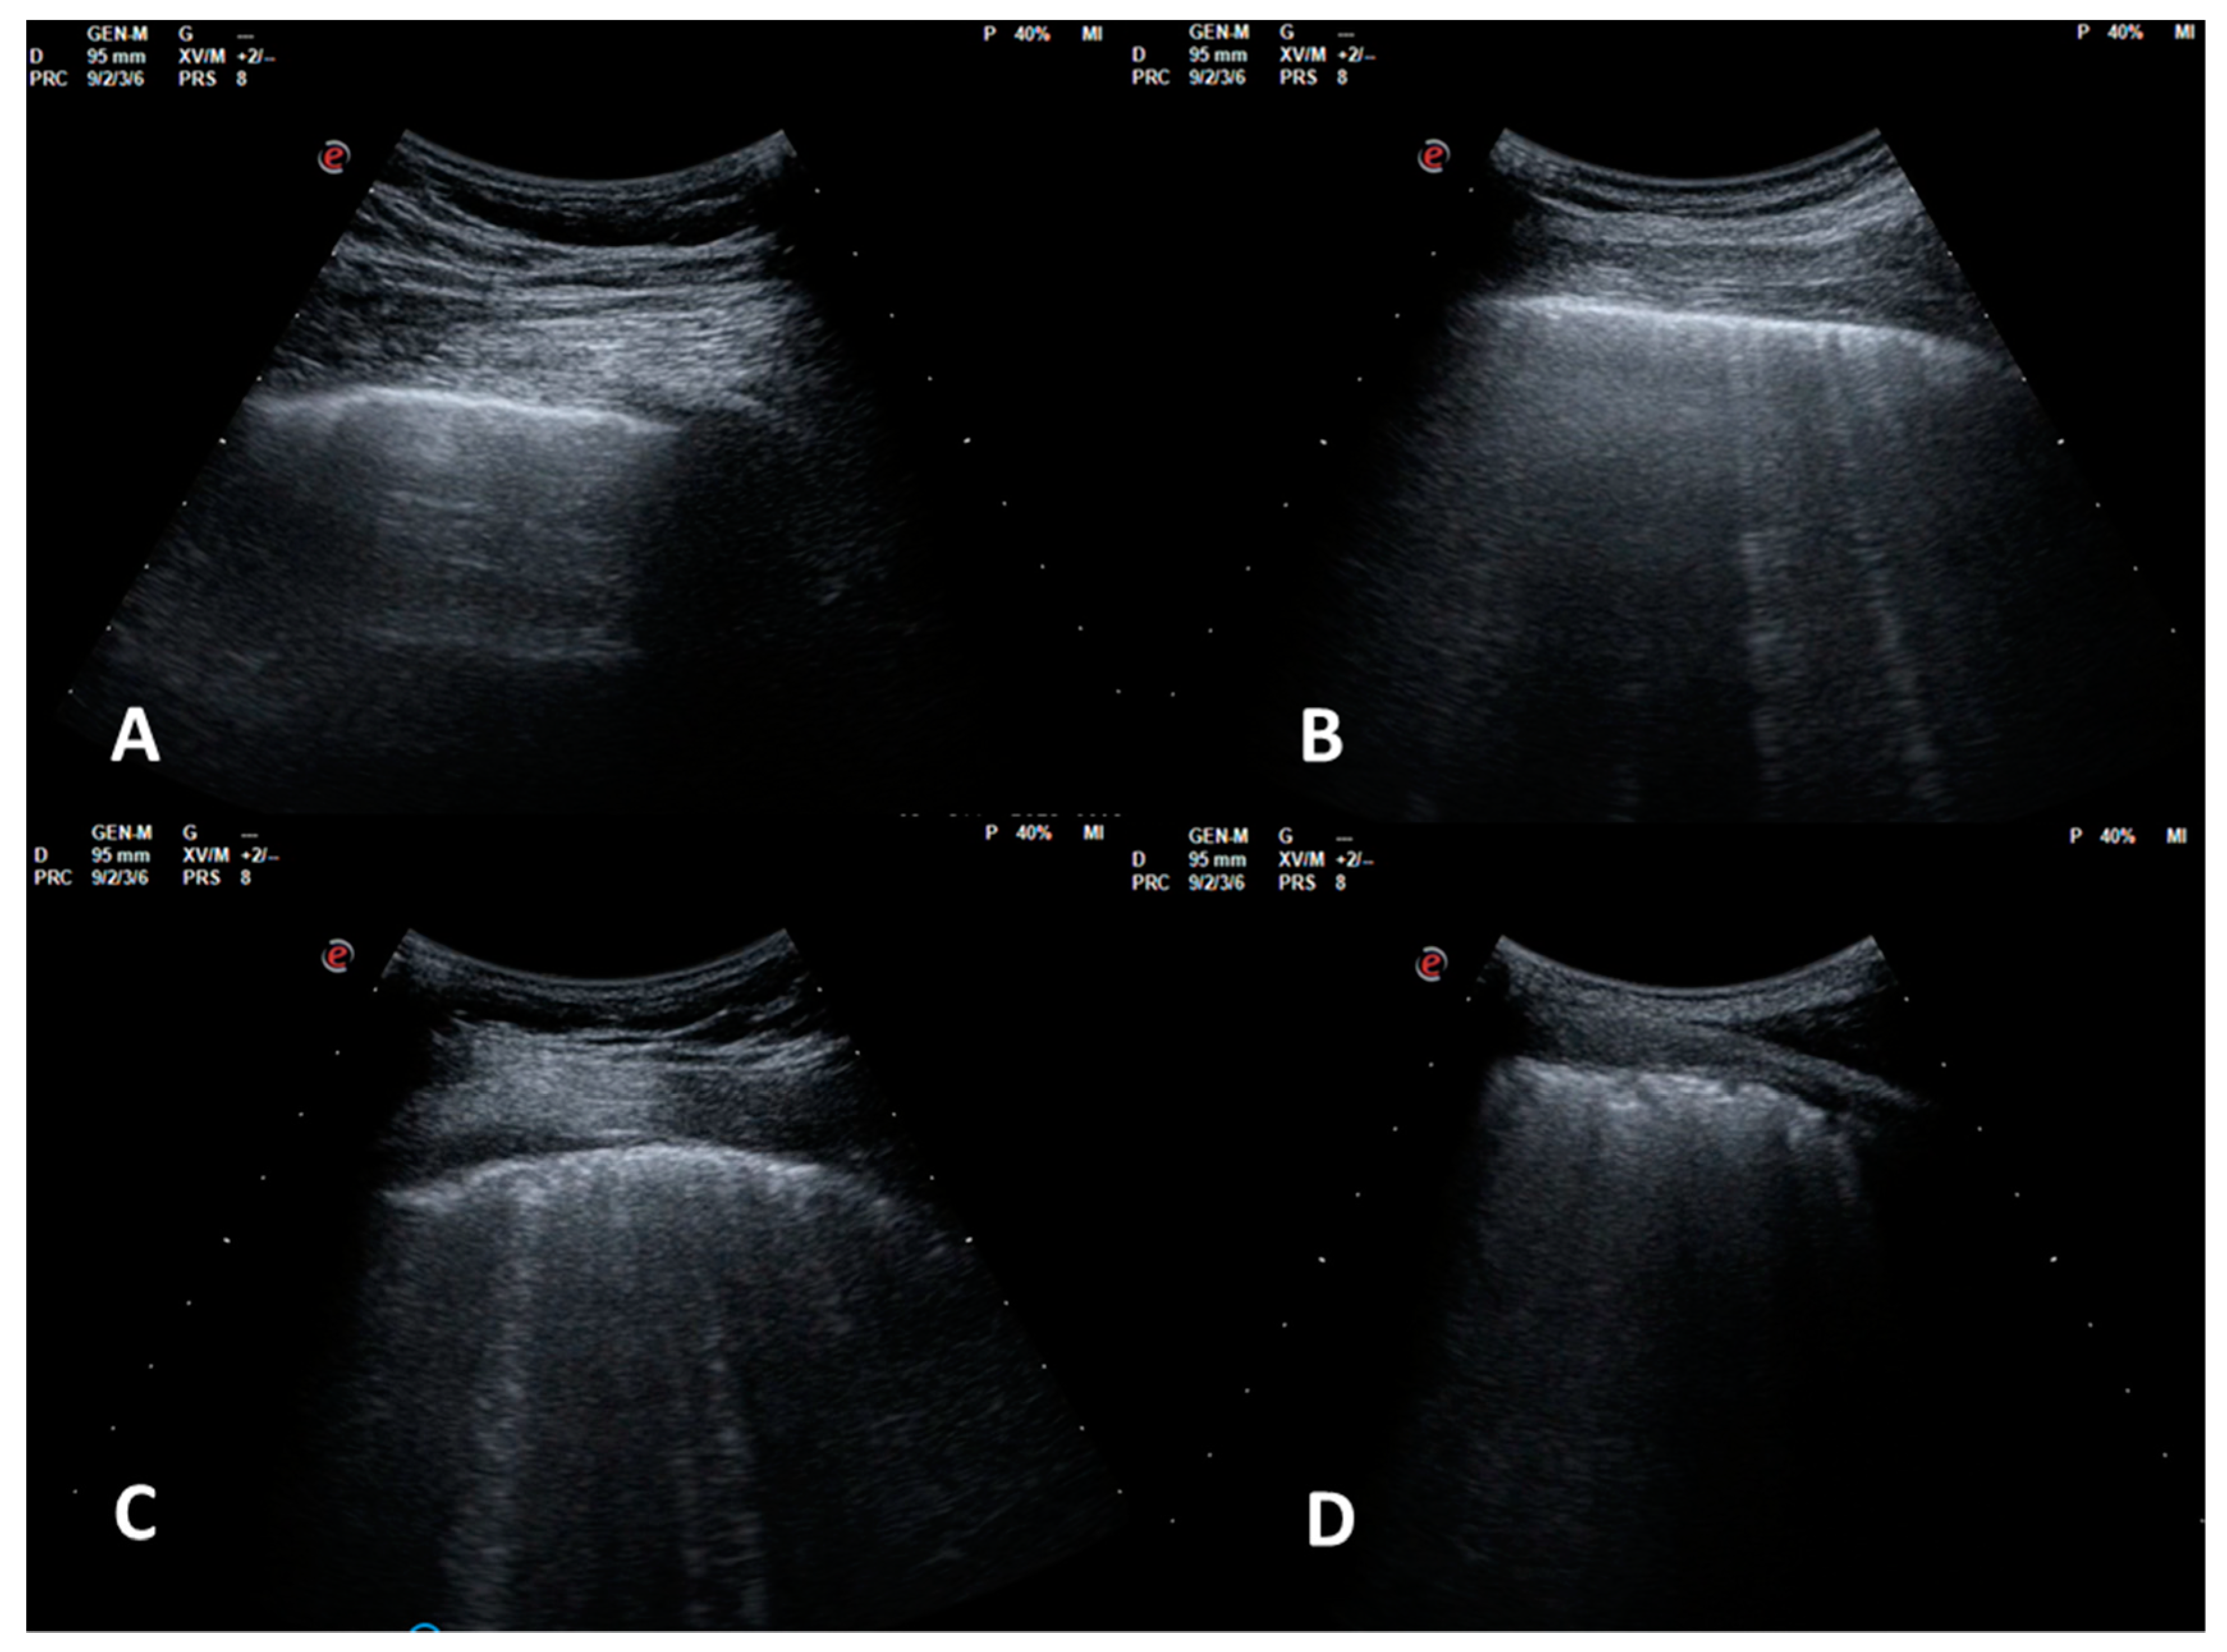

Four echographic patterns were described corresponding to worsening fibrotic changes of the peripheral lung: (1) normal or near normal; (2) SIS with predominance of reverberant horizontal artifacts; (3) SIS with vertical predominance and altered pleural line; (4) white lung with altered pleural line (Figure 1).

Figure 1. LUS patterns. (A): pattern 1, near normal; (B): pattern 2, SIS with predominance of reverberant artifacts; (C): pattern 3, SIS with vertical predominance and altered pleural line; (D): pattern 4, white lung with altered pleural line.